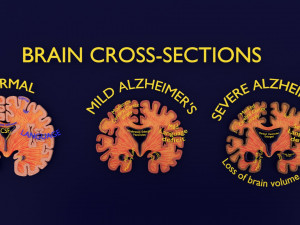

A blend model of brain along with its covering layers (meninges), skull bone and scalp labelled in detail and anatomically precise. The parts depicted are white, gray, pia, arachnoid, dura, bone, skin, fat, aponeurosis, periosteum, falx cerebri and more.